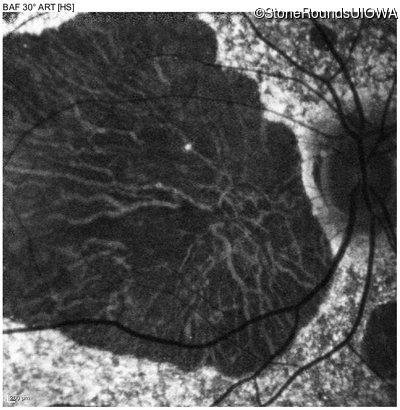

Blue Autofluorescence - Right - 10/200 sc

Exemplar